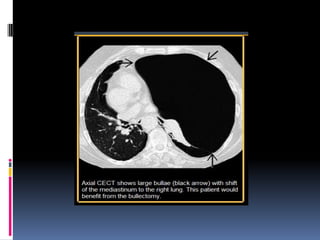

BULLA  Un espacioaéreo de más de 1 cm-por lo general de varios cm de diámetro, bien delimitada por una pared delgada que no es mayor de 1 mm de espesor. Una bulla normalmente esta acompañado por enfisema y cambios en el pulmón adyacente. Rx y TAC bulla  aparece como una lucidez redondeada focal o área de disminución de la atenuación.  Bullas múltiple están asociados con otro sg de enfisema pulmonar (centrolobulillary paraseptal).

ENFISEMA BULLOSO  enfisemabulloso es la destrucción del parénquima pulmonar, generalmente en un fondo de paraseptal o enfisema panacinar.